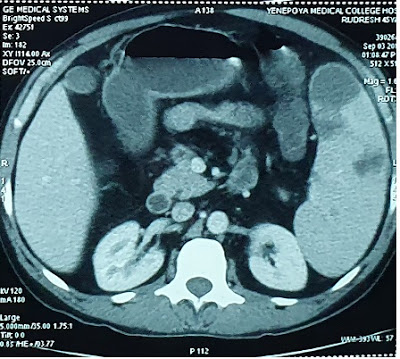

Clinical scenario: A 39-year-old female presented with a CT scan report, that read, ” multiple hypodense lesions in the liver suggestive of metastasis liver. The gall bladder, Hepatic veins, portal vein are normal. No lesion in the CBD and intrahepatic ducts are also normal”. The patient was admitted for evaluation of the primary after explaining poor prognosis to her husband thoroughly. On examination, she was conscious, oriented and deeply Jaundiced. Her vitals were stable. Her systemic examination was unremarkable.

All tumor markers CA -125, CEA and Alpha fetoproteins were elevated. For the search of the primary an upper GI endoscopy, colonoscopy including a mamogram was carried out. All turned out to be normal. While the search for the primary was on , day 4th of admission the patient was found to be incoherent, talking irrelevantly. Her arterial ammonia levels were high and she was shifted to ICU and managed as hepatic encephalopathy. Gladly , her sensorium improved after 3 days and a liver biopsy was planned for evaluation of liver lesions. Keeping in view her high INR 4 units of FFP were transfused and transjugular liver biopsy was done.The Liver biopsy was suggestive of Autoimmune hepatitis a great surprise to one and all.

She was given oral steroids and her Liver function tests improved. Repeat Ultrasound of the abdomen showed clearance of liver lesions